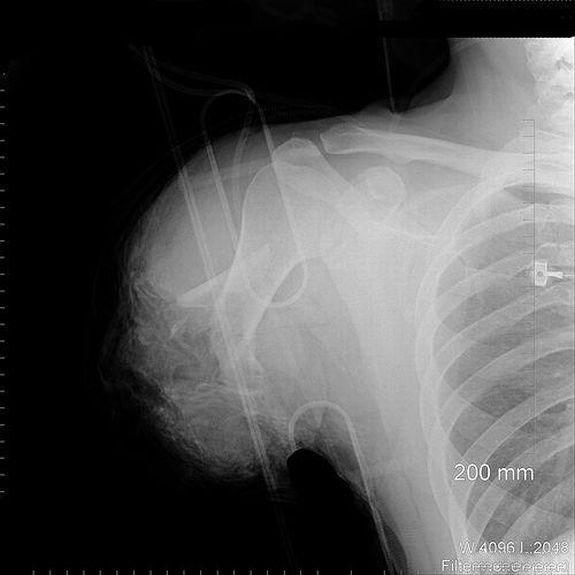

1. AP and lateral radiographs of a patient with a large glass graduated cylinder inserted into the rectum and sigmoid colon.

2. Same as 1.